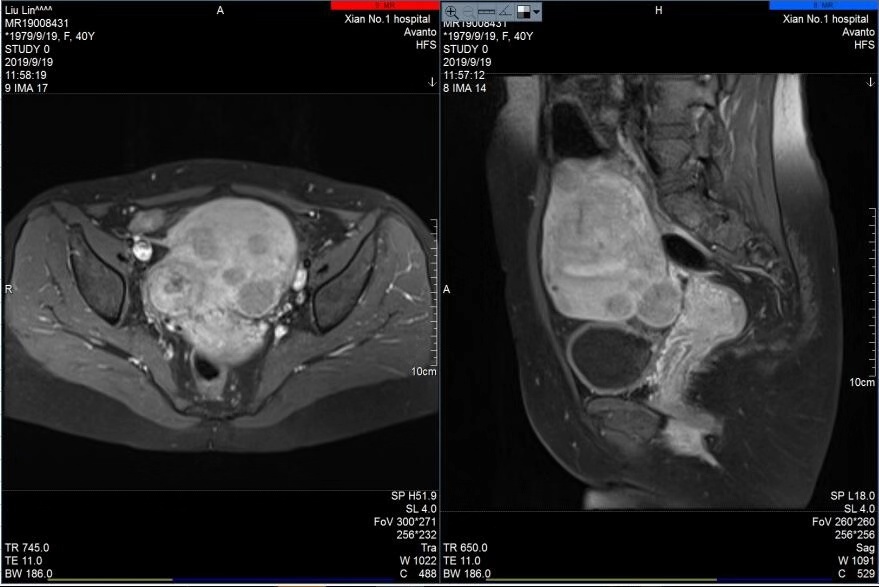

宋迎春主任在海扶刀治疗中心通过对其肌瘤进行上机定位与评估,患者完善了各项入院检查与胃肠道准备后,于2019年9月20日对其肌瘤进行海扶消融治疗,术中只用了752秒的辐照时间,就成功消融了7个肌瘤和1个腺肌瘤病灶,瘤体最大者近7cm,最小肌瘤约1cm,术前术后超声造影显示肌瘤大范围消融坏死,手术达到预期效果,患者十分满意。